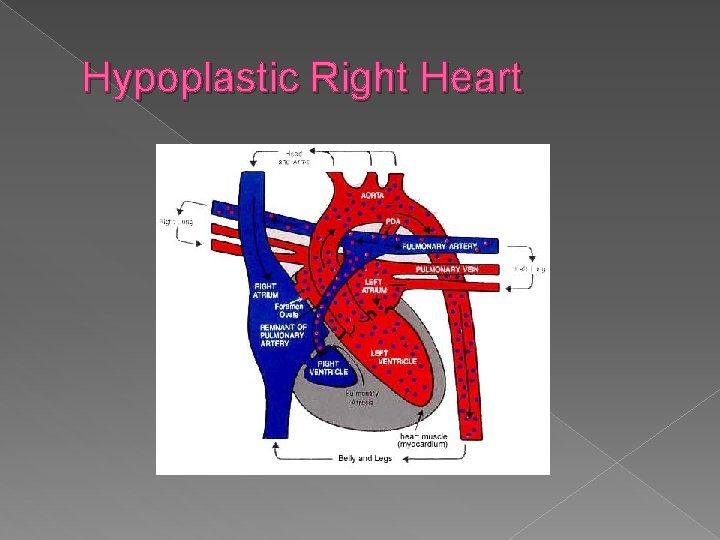

Hypoplastic Right Heart Syndrome � Generally occurs secondary to pulmonary atresia, with an intact interventricular septum. � Sonographic findings: � Absent or markedly small right ventricle on 4 chamber view � Absent or small pulmonary artery

Hypoplastic right heart syndrome › Absent or markedly small right ventricle on 4 chamber view › Absent or small pulmonary trunk

Hypoplastic Right Heart